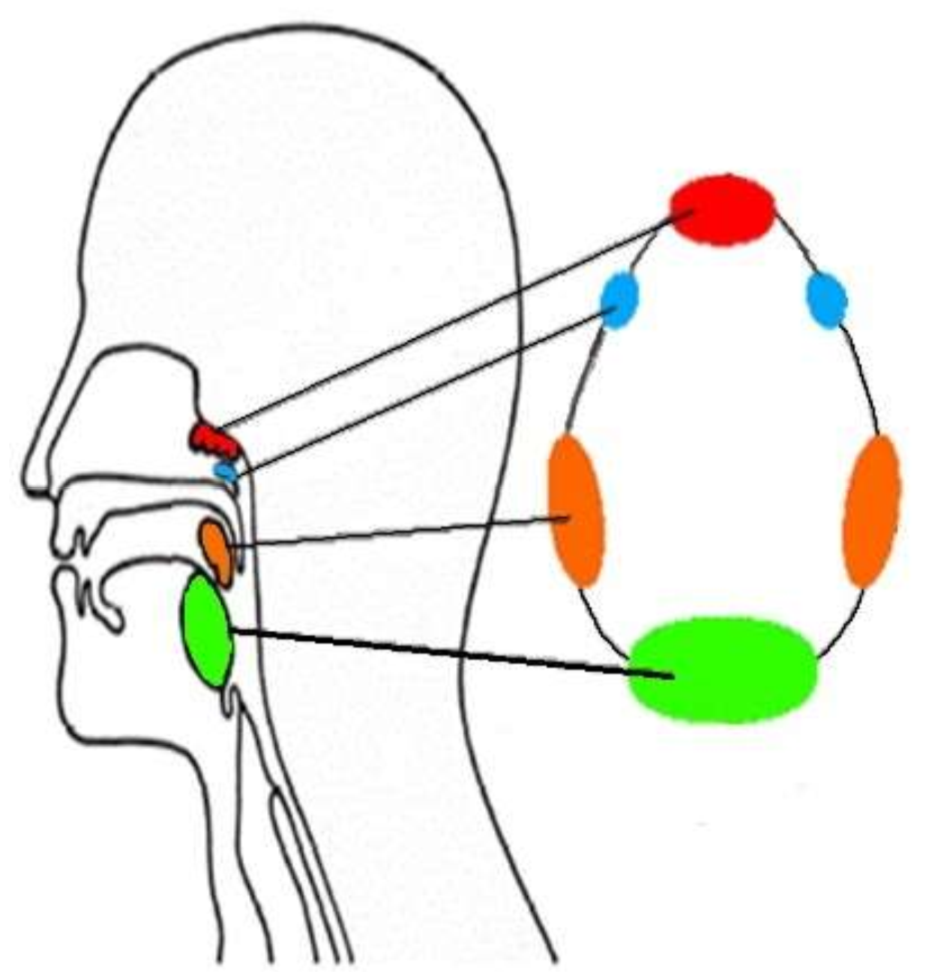

What is this group of structures called?

waldeyers ring

What is in red?

pharyngeal tonsil

What is in blue?

tubal tonsils

What is in orange?

palatine tonsils

What is in green?

lingual tonsil